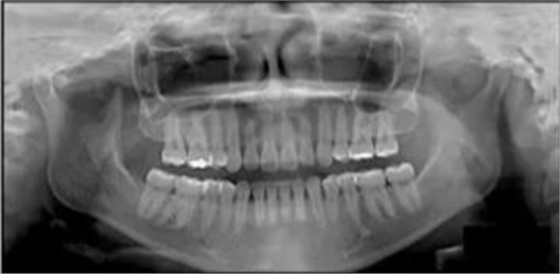

3.測量分析:治療前記錄提示該患者左右磨牙與尖牙為安氏II類關(guān)系,上頜牙弓重度擁擠,下頜牙弓輕度擁擠,深Spee曲線。6.3mm深覆蓋,80%深覆合。牙齒無齲,無第三磨牙。

治療后全景片提示間隙得到關(guān)閉,除了左下頜第一前磨牙外牙根平行度可,無明顯骨及牙根吸收。(圖7)